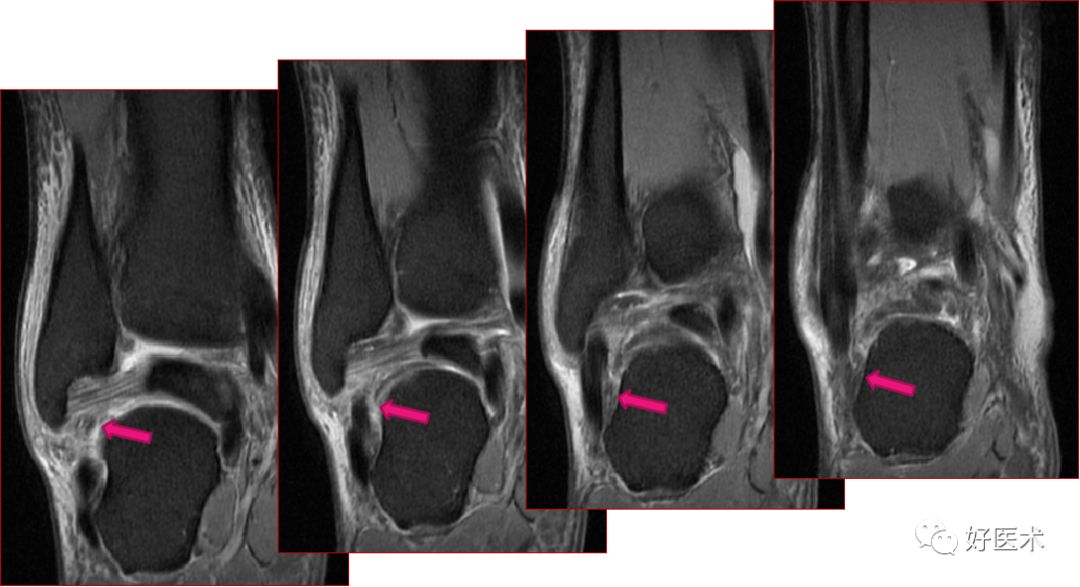

足底腱膜炎(跖腱膜炎)

正常足底腱膜

足底腱膜炎MRI表现

足底腱膜炎:注意跟骨内侧结节的局限性水肿